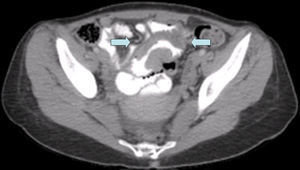

Presentamos el caso de una mujer de 32 años, sin antecedentes médicos de interés, que durante la gestación consulta en varias ocasiones por astenia, cefaleas y dolor hipogástrico. Se detectan cifras disminuidas de hemoglobina, como único hallazgo, por lo que se diagnostica de anemia secundaria a la gestación, debido a la normalidad en las cifras de controles previos. Ante la persistencia de la sintomatología tras el parto, se realiza un estudio con tomografía computarizada y se encuentra una masa de 16×7cm de diámetro yeyuno distal-íleon proximal con adenopatías mesentéricas y lesiones nodulares hepáticas (fig. 1). Dados los hallazgos clínicos, se decide realizar una intervención quirúrgica. Se evidencia una masa exocítica y ulcerada en el yeyuno distal junto a múltiples adenopatías mesentéricas, granulaciones sobre el peritoneo parietal y las lesiones hepáticas ya conocidas por la tomografía computarizada. Se realiza resección segmentaria y anastomosis primaria, incluida esta tumoración. Durante el postoperatorio desarrolla episodios de febrícula nocturna que se resuelven con tratamiento médico, y alcanza la estabilidad clínica y el alta domiciliaria a los 6 días. El estudio histopatológico informa de un tumor maligno de células pequeñas fusiformes, con infiltración extrínseca que afecta a más del 70% del espesor de la pared intestinal. Con marcadores c-kit negativo, S-100, vimentina y NSE positivos, todo esto compatible con el TMVNP (fig. 2). El mes posterior a la intervención inicia un tratamiento quimioterapéutico con doxorrubicina y se revalúa tras 3 y 6 ciclos como enfermedad no progresiva. La paciente fallece al año del diagnóstico a consecuencia de un fallo renal agudo, secundario a un síndrome nefrótico paraneoplásico.